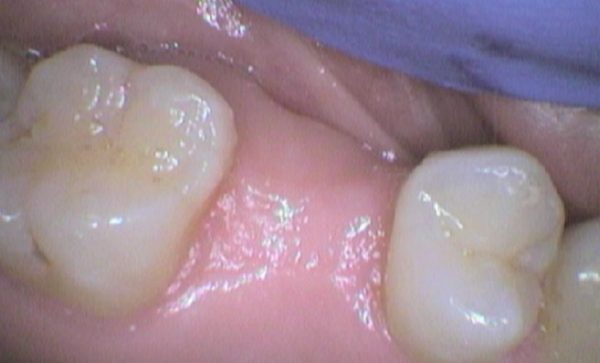

Case 29